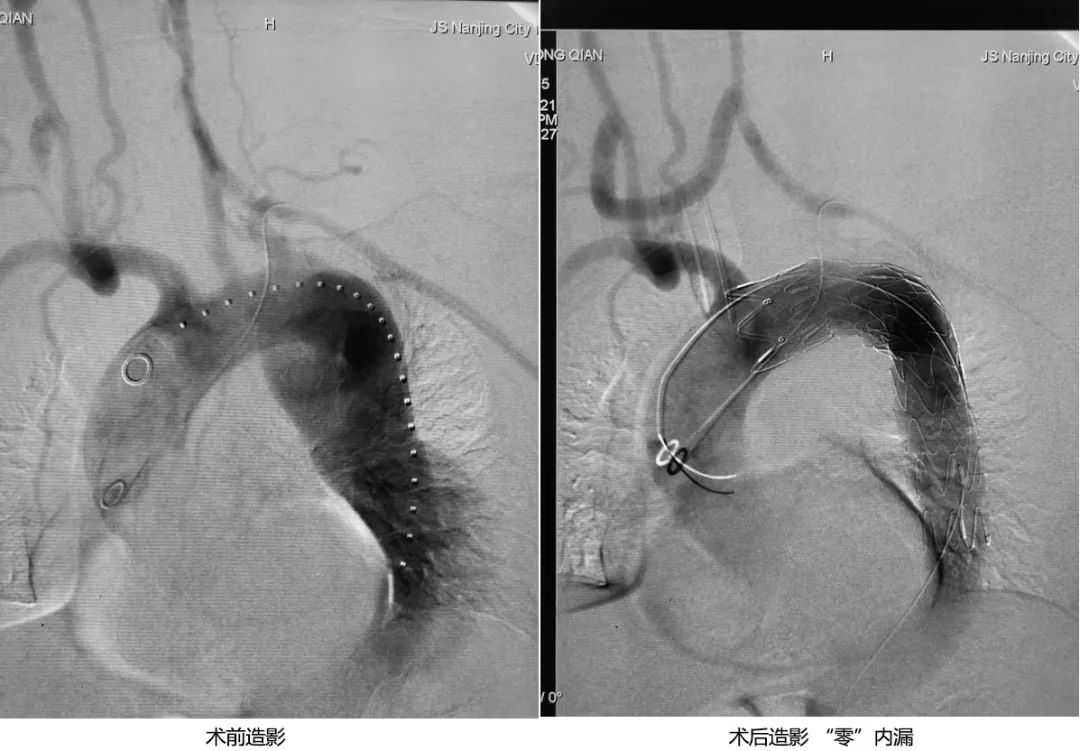

患者为46岁男性,体检发现胸主动脉夹层动脉瘤3周,主动脉CTA示:主动脉夹层动脉瘤(Stanford B型),夹层动脉瘤明显扩张直径约6.1cm,属于破裂高危,手术指征明确。

张雷杨教授团队首先采用微创介入的方法治疗夹层动脉瘤,但患者的主动脉夹层动脉瘤累及了左锁骨下动脉和左颈总动脉开口,要充分隔绝夹层动脉瘤,必然会影响上述两个重要血管的血供。目前重建主动脉弓部多支血管的主要方法有开窗技术、烟囱技术和杂交技术,这几种方法各有优缺点,有不同的适应症。针对该患者,由于夹层动脉瘤巨大,首先是要保证术后不能有近侧I型内漏,其次,患者的左颈总动脉起始部和左锁骨下动脉异常扭曲,导致原位开窗困难。所以,张雷杨教授团队决定采用杂交技术,手术方案为:先行右颈总动脉-左颈总动脉搭桥+左颈总动脉-左锁骨下动脉搭桥,然后行TEVAR(主动脉夹层腔内隔绝术)。

图片

术中,在杂交手术室,张雷杨教授团队首先在颈部经三个小切口,顺利完成了颈颈搭桥和颈锁搭桥;然后经股动脉行TEVAR(主动脉夹层腔内隔绝术),把支架锚定区延长至无名动脉远侧缘。术后造影提示主动脉夹层动脉瘤隔绝效果完美,“零”内漏,而且两根桥血管通畅,血流流速、流量均满意!